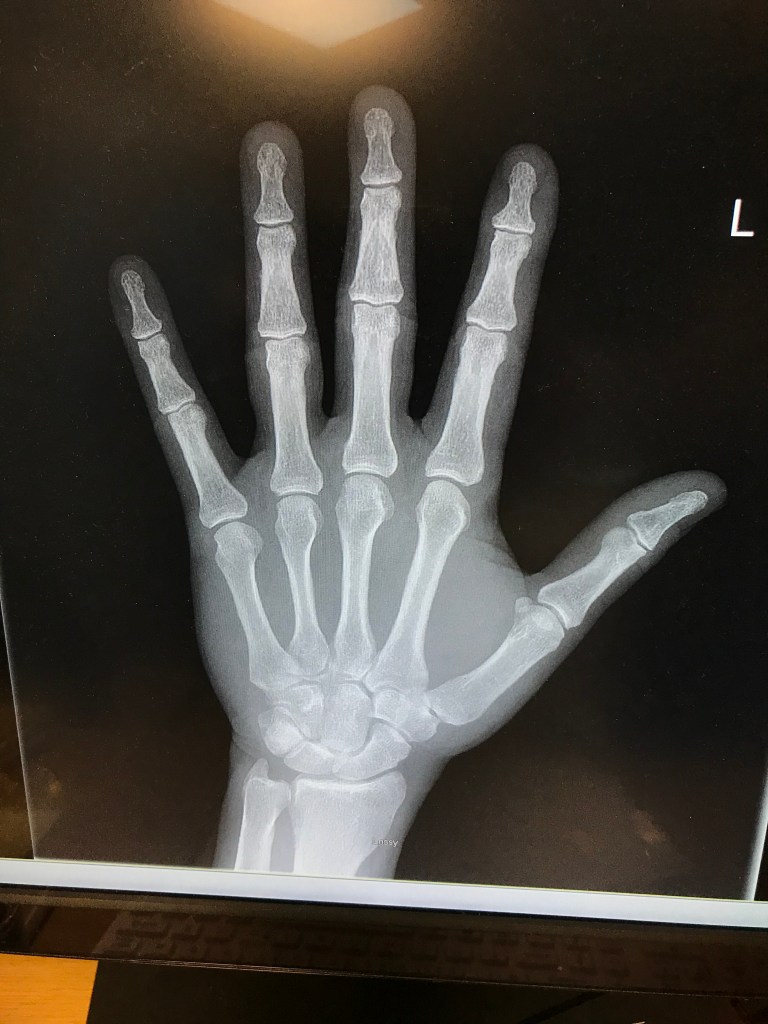

The first of the three images here was taken shortly after the spaniel and I parted company, and shortly before I hoofed it over to the local medical centre for a clean-up, dressing and tetanus booster. The second one was yesterday, when the first dressing was removed, and the x-ray was taken in hospital not long after. My doctor was not happy with the swelling and heat, and reckoned as a precaution it would be good to get a blood test and a change of antibiotic.

And so I had to scoot into Dublin to one of the major hospitals in the middle of wave three. But they were great, I have to say. Bloods and x-ray turned around within an hour or two, and a new dressing and change of antibiotic. The doc was happy not to admit me, and so was I.

OMG, Dec! Well … your bones look lovely, anyway.

The doc was very impressed with my bones 🙂